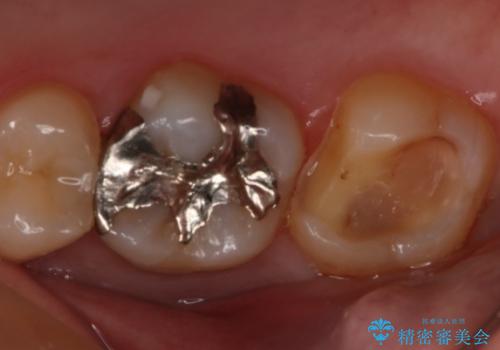

- 右上大臼歯の再治療を希望され来院された患者様です。

切削量と形状を考慮し、インレーでの治療を計画しました。

患者様がゴールドを希望されたのでゴールドインレーを選択しました。